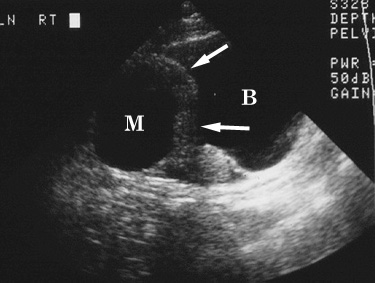

Figure 1. Longitudinal transabdominal sonogram shows a thick-walled (arrows) cystic right adnexal mass (M) superior to the urinary bladder (B). |